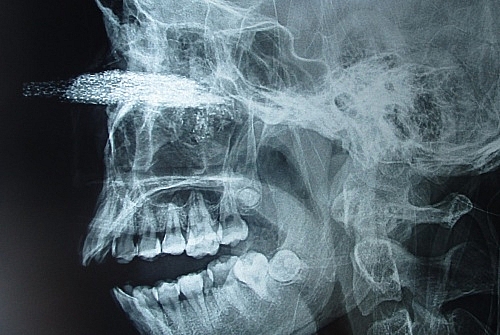

Với tình trạng một phần lưỡi cưa găm vào giữa mặt ở vị trí gốc mũi và hai mắt, các bác sĩ khoa Phẫu thuật Hàm mặt - Tạo hình - Thẩm mỹ, Bệnh viện Hữu nghị Việt Đức xác định, mắt trái bệnh nhân vẫn nhìn được, mắt phải phù nề nhiều.

| Hình chụp X-quang cho thấy lưỡi cưa găm vào mặt bệnh nhân |

Các bác sĩ đã hội chẩn, quyết định phẫu thuật lấy dị vật, xử lý tổn thương cho bệnh nhân ngay. Phần lưỡi cưa kích thước khoảng 10x12 cm cắm sâu vào xoang hàm trên, có nhiều dị vật nhỏ.